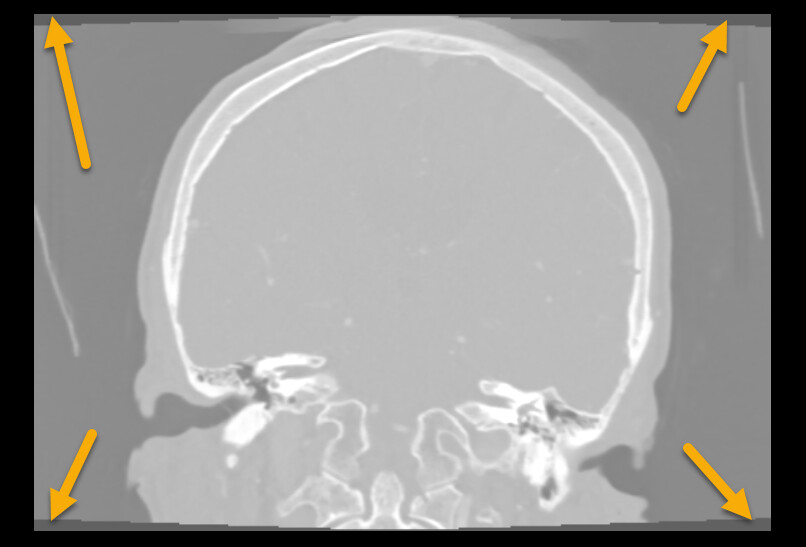

• Most registration methods generally require the images cover the same region. Your images do not meet this requirement. To fix this, probably the easiest is to crop the images to approximately to the same region.

• The image edges coincide edge of anatomy (skull touches the image edge). This is an issue because image processing methods often need to extrapolate a little bit beyond the image region and this extrapolation will fail if the intensity near the image edge is non-uniform (it is fine if the image edge cuts through the middle of tissue or cuts through the middle of air, but the image edge should not be at an anatomical region boundary).

• There is resampling artifact near the image edges. It would be better to cut them off.